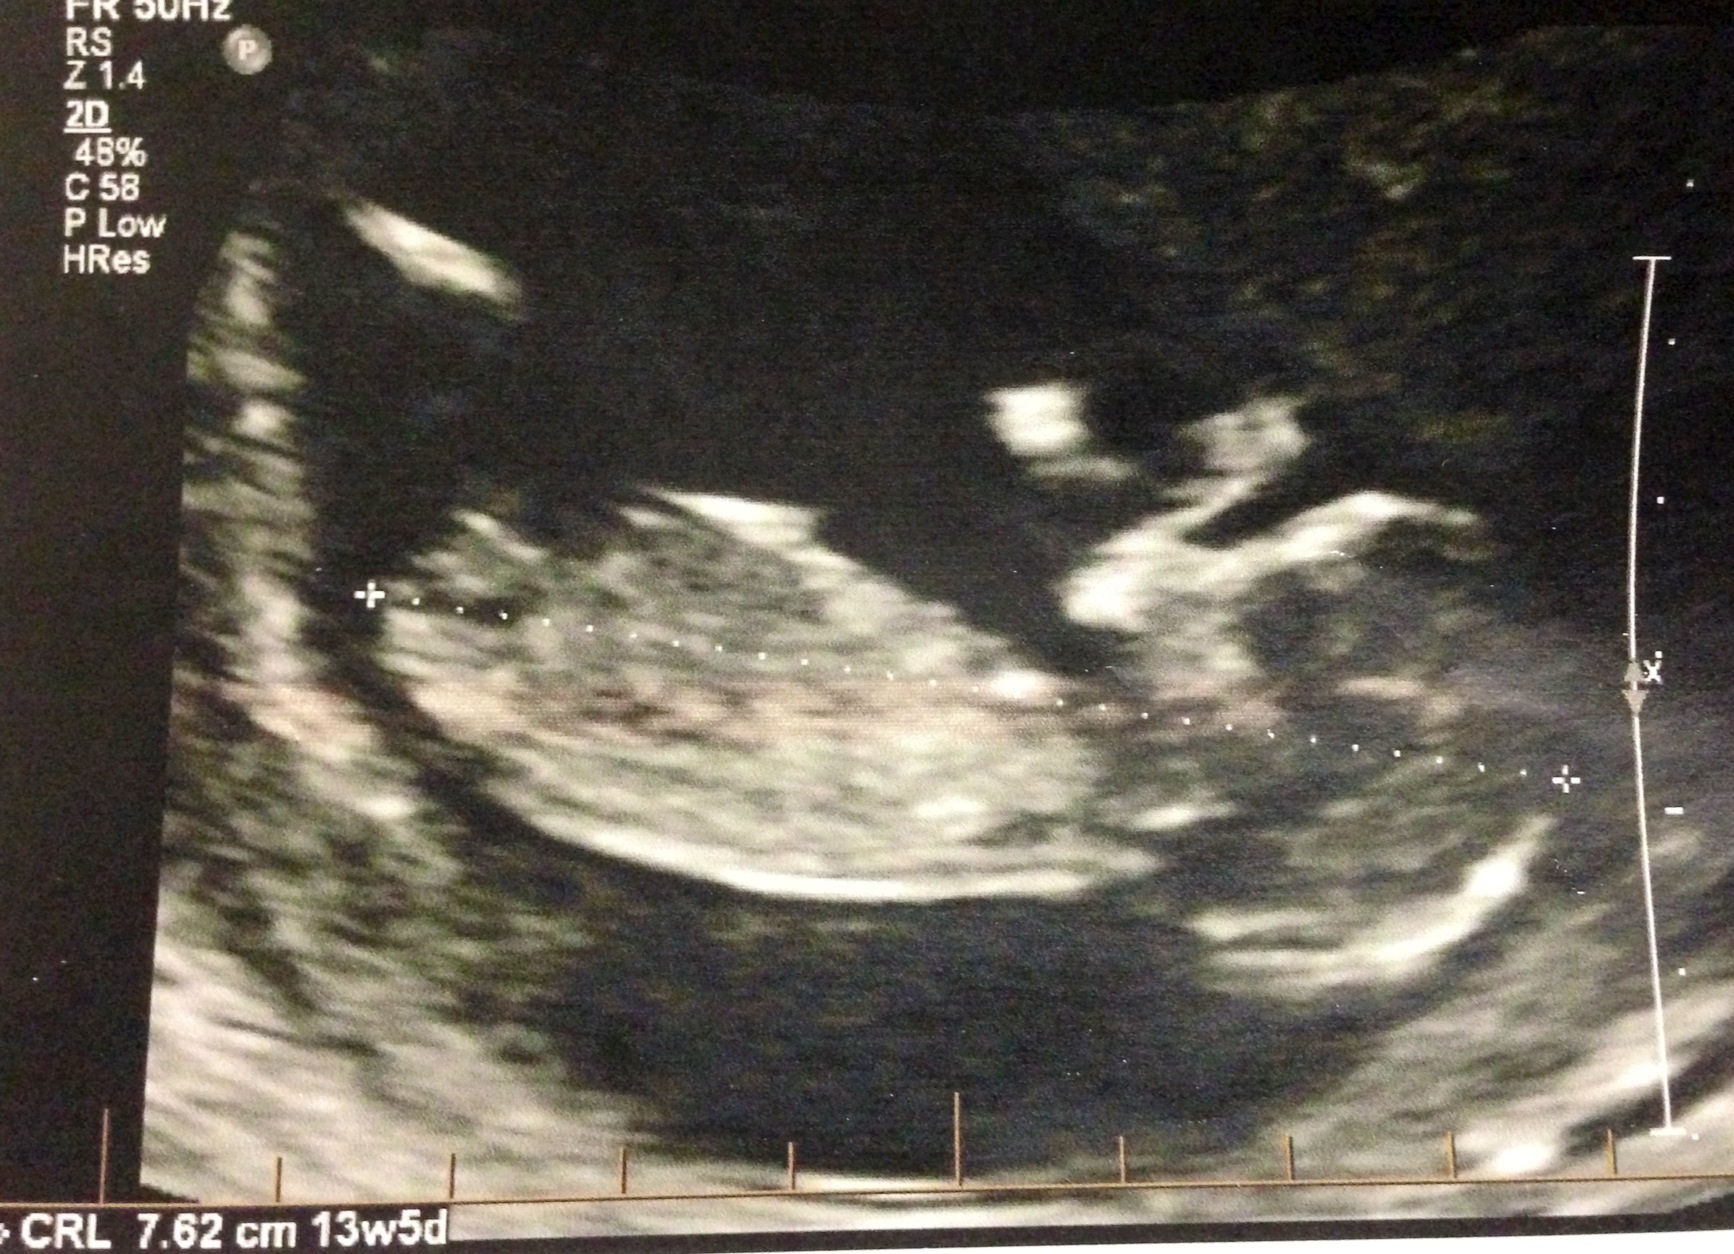

After I told tech I had 3 boys she said 55% girl.

What does anyone who knows what they are looking at think?

She may have seen or not seen something the pic isnt showing, but that pic seems to have a boy bobble on to me, but then that bobble could be part of the leg as it seems to be in alinement to it? Any other pics??:)

The more I look the more I think the bobbles part of the leg, its just the wrong shape for a boy nub? So I guess girl:)

These are seriously the best I got. Baby was facing down, and jumping and had legs tightly closed. Tech literally seen something on the potty shot she brought up( no photo) I was about to leave and she said I'd guess girl 55%.